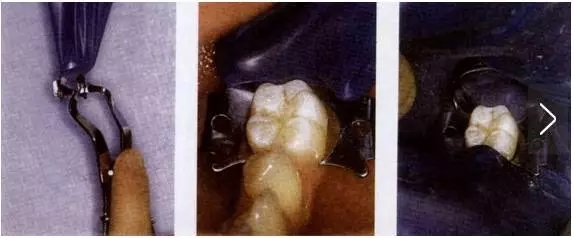

1、翼法(wing technique)

在口外用橡皮障支架撐開打好孔的橡皮布,將橡皮障夾的翼穿過橡皮布的孔并用橡皮障夾鉗撐開,將橡皮障夾和橡皮布一同安放到需要隔離牙齒的頸部。

橡皮障夾的喙應(yīng)位于牙齒的外形高點(diǎn)下方,與牙齒有四點(diǎn)接觸,否則橡皮障夾容易轉(zhuǎn)動(dòng)和滑脫。

此法為口內(nèi)內(nèi)操作時(shí)間最短的一種方法,因此最為常用。